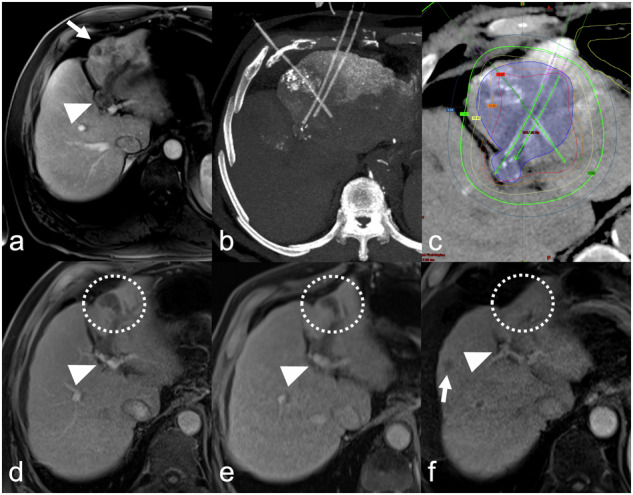

Methods: From January 2010 to January 2022, 56 patients (median age 67.5 years) with HCC and PVTT underwent 64 procedures. PVTT was further classified according to the Japan liver cancer study group into VP1-VP4. Tumor response was evaluated by cross-sectional imaging 6 weeks after CT-guided HDR brachytherapy and every 3 months thereafter. Local tumor control (LTC), progression-free survival (PFS), and overall survival (OS) were assessed using Kaplan-Meier curves. The severity of procedure-related complications was classified according to the Society of Interventional Radiology guidelines.

Results: Patients were available for imaging evaluation for a median follow-up of 14.0 months. The median diameter of the largest lesion was 56 mm. Estimated median PFS, LTC, and OS were 7.0 (95% CI 5.0-13.0), 14.0 (95% CI 7.0-21.0), and 20.0 (95% CI 13.0-26.0) months respectively. Actuarial 1-, 2-, and 3-year OS rates were 66%, 41%, and 27%, respectively. Subclassified for VP1, VP2, VP3, and VP4 estimated OS was 38.0 (95% CI 9.0-Not-a-number), 21.5 (95% CI 15.0-25.0), 15.0 (95% CI 7.0-33.0), and 13.0 (95% CI 6.0-34.0) months, respectively. Considering the 64 procedures, we recorded no complications for 49 (76.6%), mild-to-moderate complications for 12 (18.8%), and major complications for 3 (4.7%).

Conclusion: CT-guided HDR brachytherapy was safe and effective for locoregional treatment in patients with advanced HCC due to PVTT, achieving long-lasting local tumor control.